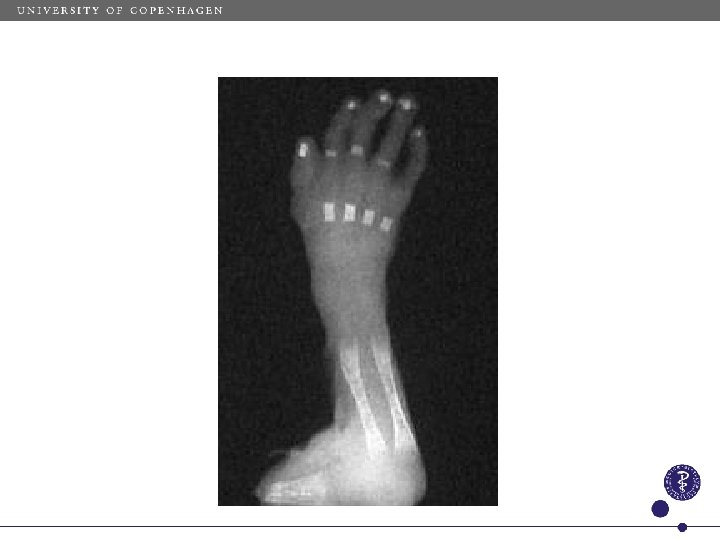

Turner syndrome hand